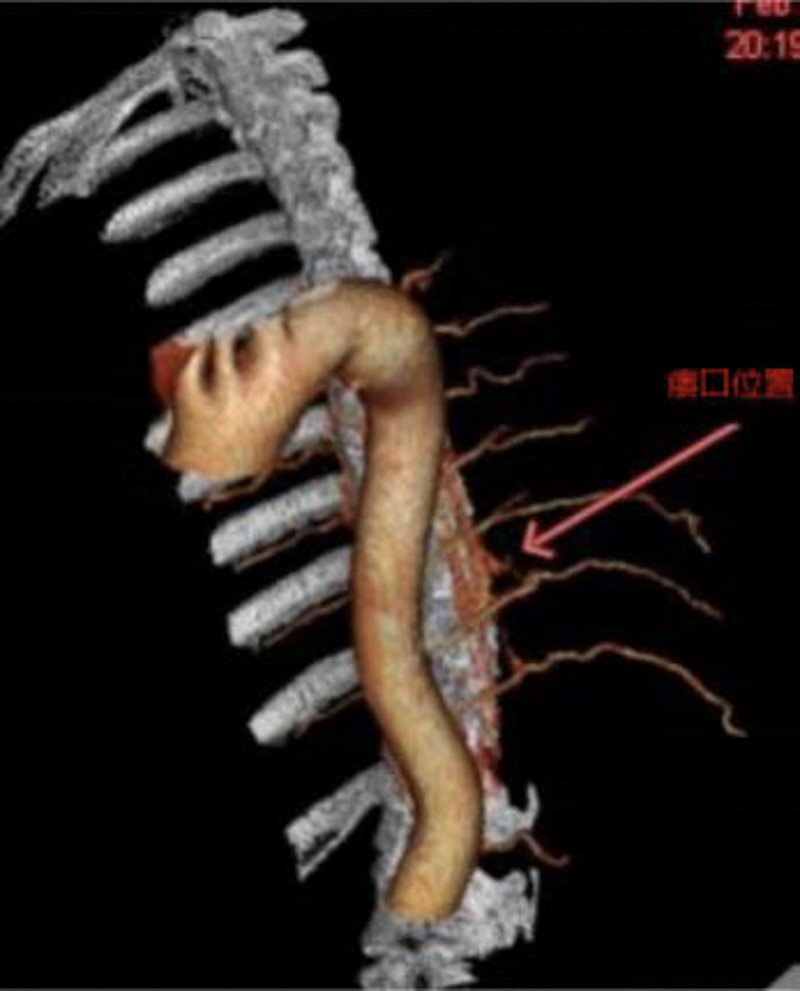

救治刻不容緩,醫(yī)院立即組織神經(jīng)外科、神經(jīng)內(nèi)科及麻醉科等開(kāi)展多學(xué)科會(huì)診,結(jié)合方先生的情況綜合判斷,為他設(shè)計(jì)了治療方案,經(jīng)胸髓CTA、血管造影,明確瘺口在胸10椎體水平,決定實(shí)施顯微鏡小切口半椎板入路手術(shù)切除瘺口。

方案確定后,團(tuán)隊(duì)第一時(shí)間為田先生實(shí)施了微創(chuàng)手術(shù),術(shù)中可見(jiàn)脊髓表面較多異常迂曲擴(kuò)張的回流靜脈,準(zhǔn)確定位找到問(wèn)題所在,造成下肢乏力的小瘺口僅有幾毫米,醫(yī)生在顯微鏡下精雕細(xì)琢,將異常的瘺口阻斷切除,脊髓及脊神經(jīng)根保護(hù)完好,術(shù)中回流靜脈壓力明顯下降。手術(shù)僅需2.5cm小切口,磨除小部分椎板,完整保留關(guān)節(jié)突關(guān)節(jié),不影響脊柱穩(wěn)定性,無(wú)需“打釘”固定,完全保留患者的脊柱活動(dòng)度。